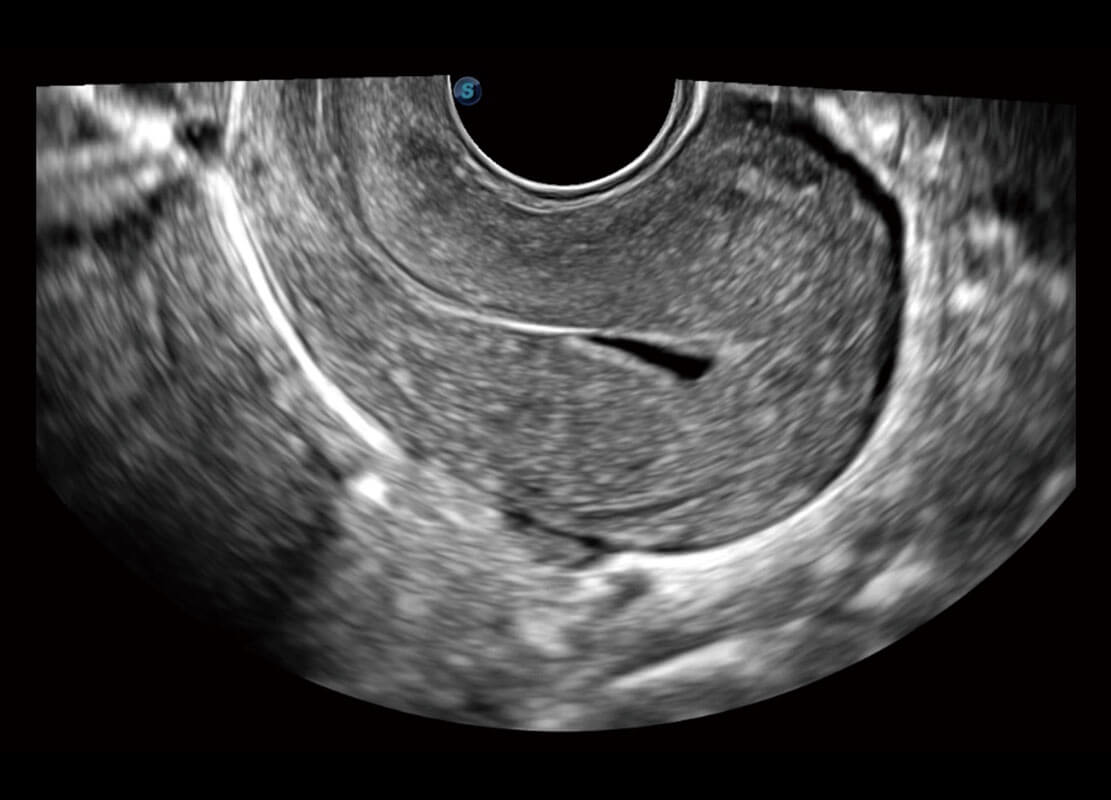

P60优异的图像质量搭载专科探头,在妇科基础疾病的诊断、卵泡生长的监测、输卵管通畅情况的判别等方面为您提供生殖应用方案。

腔内三维-光影成像